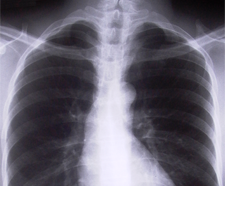

Long, hart en vaatziekten vmbo-kgt34